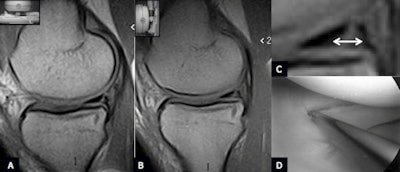

| Unstable longitudinal traumatic tear of the medial meniscus posterior horn. (A) Sagittal scan plane PD-W in the supine position shows a longitudinal tear of the posterior horn of the medial meniscus. (B) Sagittal scan plane PD-W in the weight-bearing position shows the increased intrameniscal extension of the lesion on the axial plane: See magnification from image B in C (arrow). (D) Arthroscopy confirms unstable traumatic longitudinal tear of the medial meniscus posterior horn. |

The authors retrospectively reviewed and analyzed 20 MRI exams of normal knees and 57 MRI exams of knees with clinical evidence of tears of the medial meniscus. In the same session, after conventional 1.5-tesla and dedicated 0.25-tesla supine MRI examination, the patients underwent a weight-bearing examination with the same dedicated MRI unit. In all cases, sagittal and coronal proton-density weighting were used. All patients underwent arthroscopy 18 to 25 days after the weight-bearing MRI.

In the first group, no statistically significant anatomical modifications of shape, intensity, and position of the medial meniscus were observed between standard 1.5-tesla, dedicated supine, and upright MRI. In group A, the images acquired in the supine position (dedicated and 1.5-tesla MRI) documented in 21 cases a traumatic tear (group 2A) and in 36 cases a degenerative tear (group 2B).

In group 2A, weight-bearing MRI showed the presence of an unstable tear in only 19 out of 36 cases. In group 2B, weight-bearing MRI showed this in only nine out of 21 cases. Arthroscopy confirmed the weight-bearing MRI diagnosis in all cases.